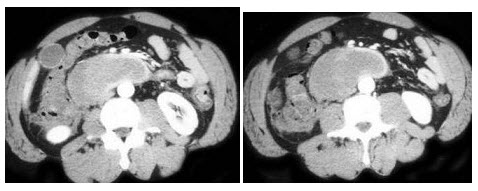

根据所提供的图像,该病例最可能的诊断为()A: 胰腺假性囊肿B: 十二指肠血肿C: 十二指肠癌D: 十二指肠憩室E: 胰腺癌

根据所提供的图像,该病例最可能的诊断为()

- A: 胰腺假性囊肿

- B: 十二指肠血肿

- C: 十二指肠癌

- D: 十二指肠憩室

- E: 胰腺癌